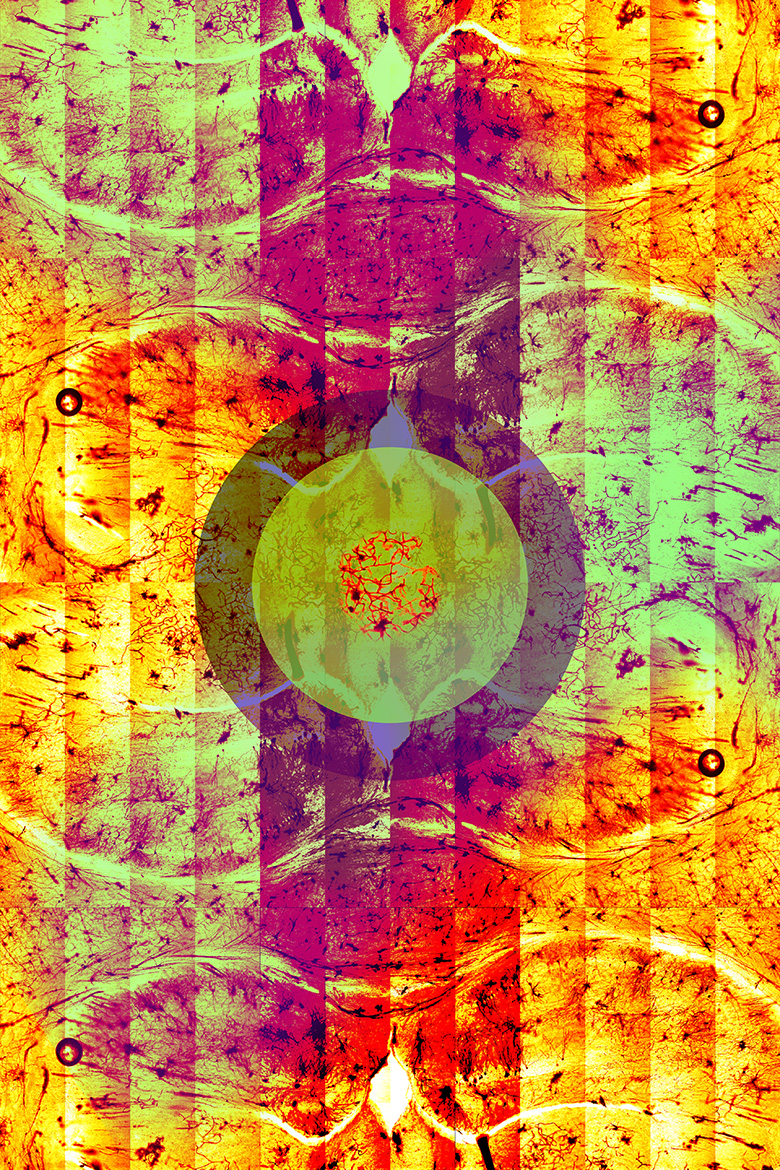

Dentate

Multiphoton Confocal Microscope Zeiss 710 microscope

For years, researchers have exploited mice as powerful genetic tools to answer long standing questions in biology. By studying the regulatory networks in the mouse brain, researchers can better understand the link between genomic mechanisms and social behavior. The original image shows a Golgi-stained mouse hippocampus—a region of the brain involved in memory—that was taken with a multiphoton confocal Zeiss 710 microscope. The characteristic black color originates from silver nitrate used in the staining process.

The researchers used Golgi staining to identify structural and organizational differences in neuronal processes of mice with a mutation in an autism susceptibility gene, Auts2. The art piece features a central cluster of neurons, called the dentate nucleus, against a backdrop

of psychedelic hippocampus. This piece pays homage to late abstract painter Helen Frankenthaler, who once said to “let the picture lead you where it must go.”